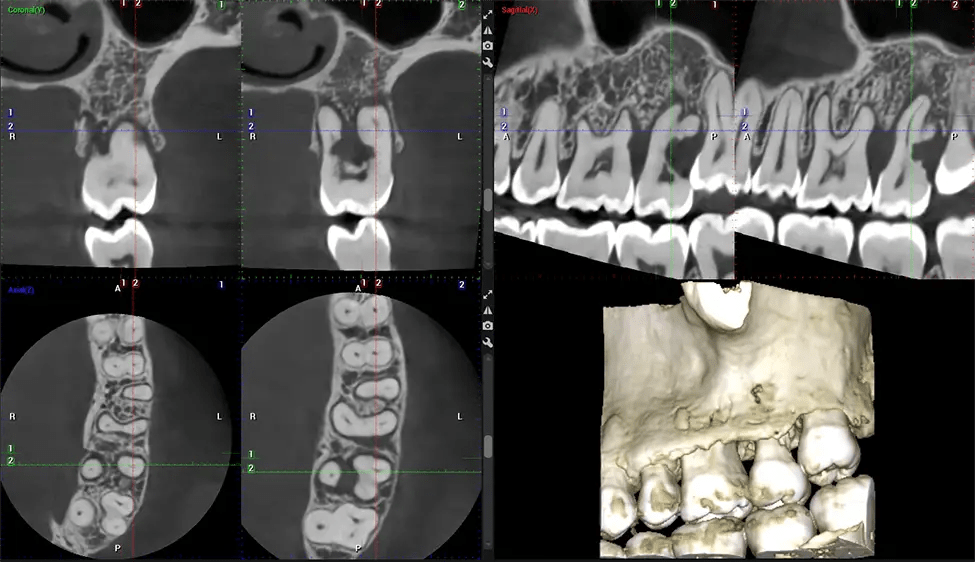

This 3D scan, called cone beam computed tomography, gives your dentist a more complete image of your oral anatomy and disease processes than a traditional X-ray. Unlike conventional X-rays, which capture a 2D image of your mouth from various angles, a 3D scan takes multiple digital X-rays for one image. It provides a complete view of your jaw, teeth, nerves, and soft tissues. This enhanced view allows dentists to detect minor issues not visible in traditional 2D scans, such as impacted wisdom teeth or bone fractures in the sinus cavity.

Another significant benefit is that 3D imaging provides more precise images of your bone structure. These images are more detailed, providing you with a more accurate diagnosis. An accurate diagnosis means better treatment for you.

When paired with extractions, dental implant placement, or bone grafting, CBCT technology can provide you with a quicker and much more comfortable experience. This is because the 3D image provides a more detailed picture of your entire oral cavity, allowing your dentist to walk you through each step of the process before it occurs. This often helps patients feel more prepared and comfortable overall, especially if they have had a traumatic experience with past dental treatments.

Our patented SCARA technology enables doctors to capture True Extraoral Bitewings that are as accurate at detecting caries as a 2D bitewing series, but with half the radiation dose. With our bitewings, doctors can view the apices of teeth on both jaws providing a more comprehensive view of the patients’ anatomy.